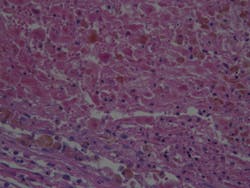

The researchers explained that healthy cells that separate from larger tissues face almost certain death through a process called anoikis unless they can reattach within hours. However, one hallmark of malignant cells is their ability to stay alive indefinitely once they separate from tumor tissue, allowing them to survive and migrate elsewhere in the body to form metastatic tumors. While detached, they form blebs indefinitely, whereas healthy cells can form blebs only for about an hour after detaching from their tissue of origin.